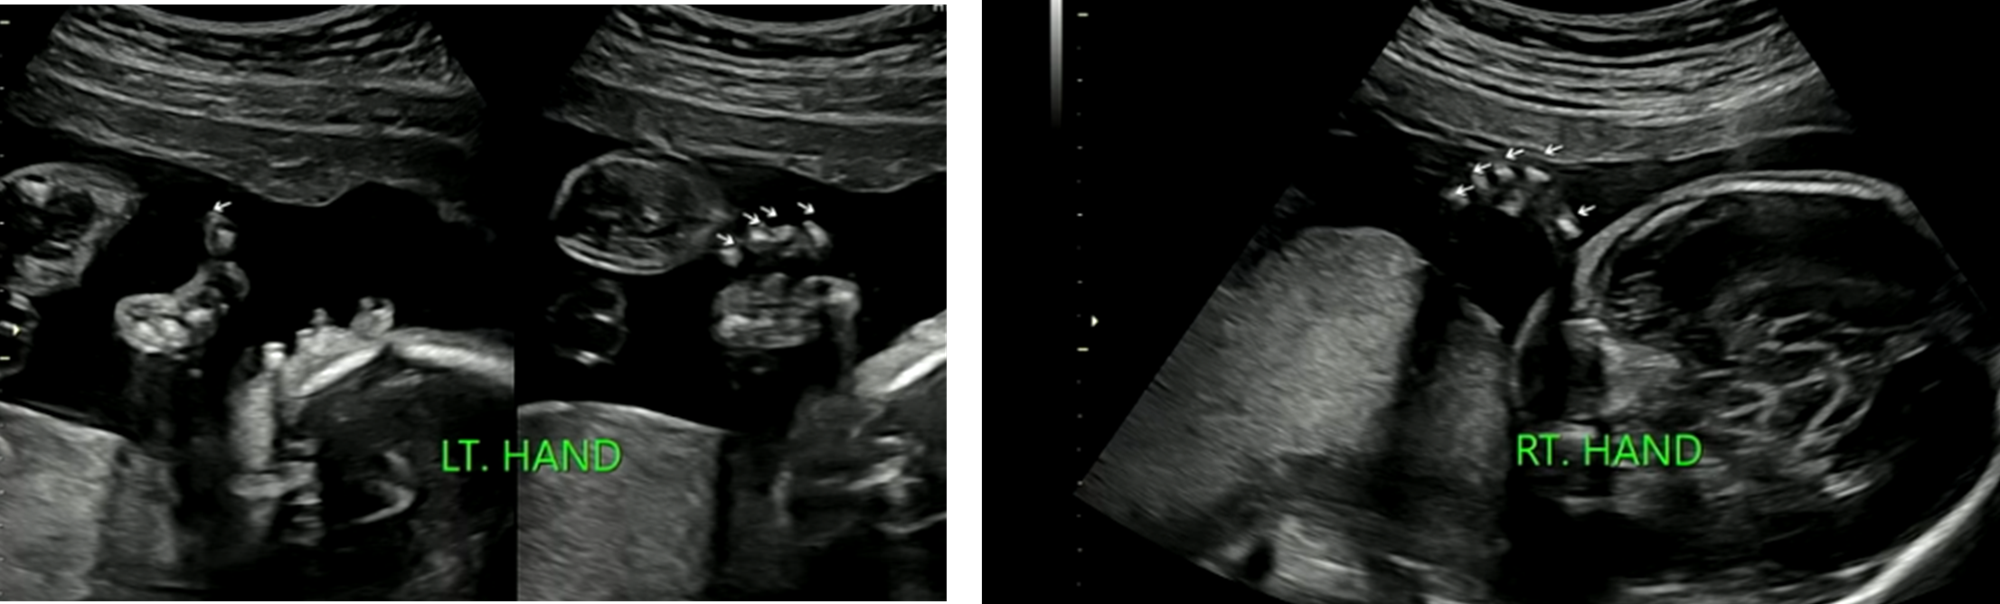

손가락

※ 초음파 용어) LT.HAND : 왼쪽 손가락, RT.HAND : 오른쪽 손가락

손가락도 5개 다 있음을 확인하였다.